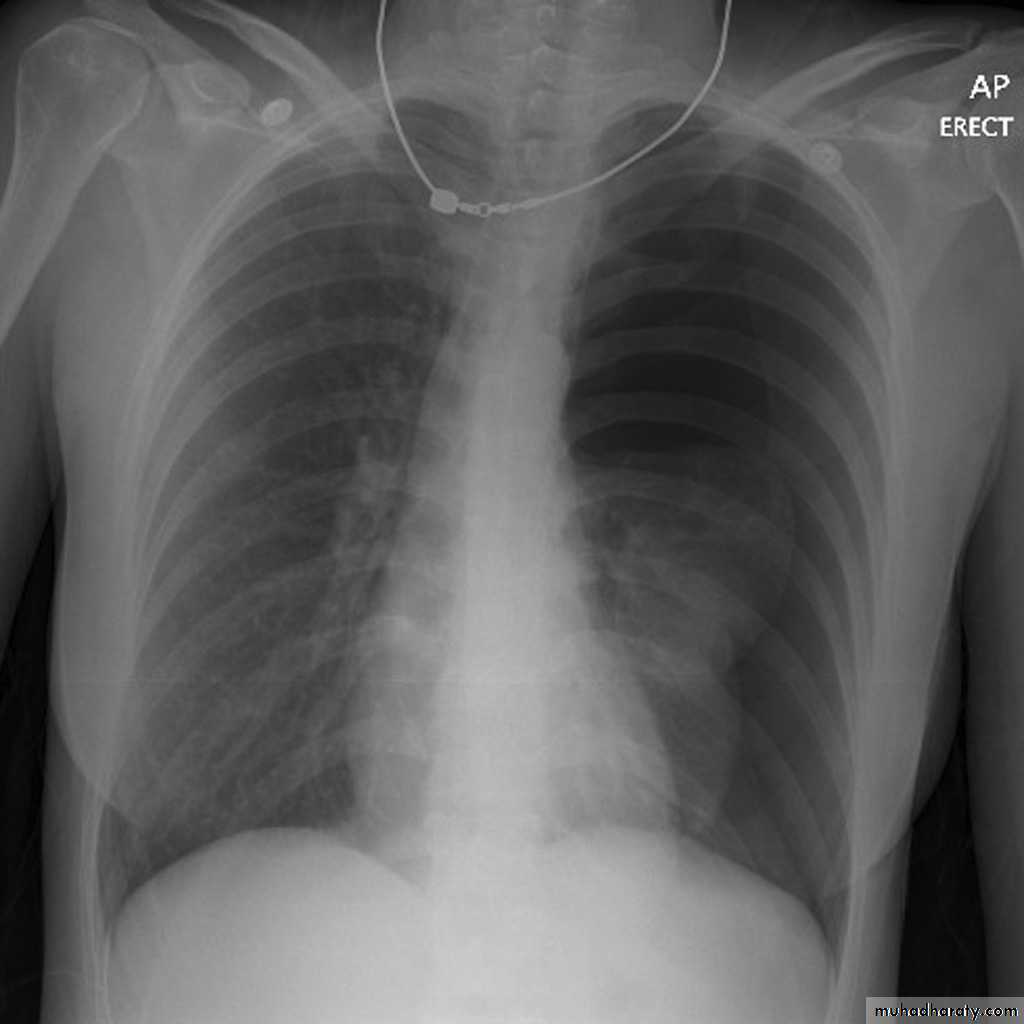

Pneumothorax

!! pneumothorax